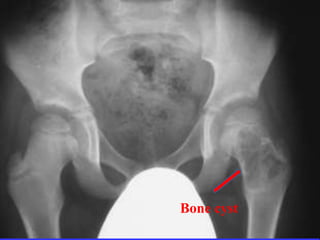

Tumors

Bone cyst